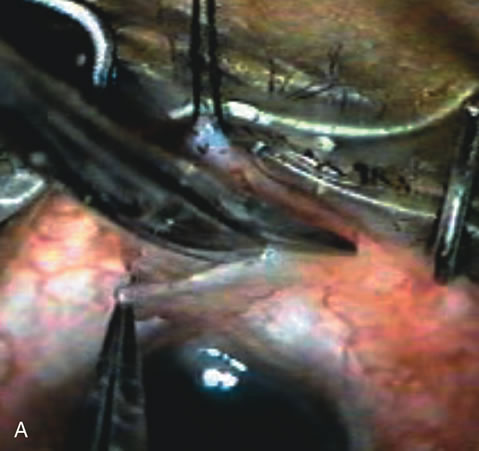

In years past, patients with both cataract and glaucoma frequently provided overwhelming surgical challenges for the ophthalmologist. The ability to carry out phacoemulsification through a 3.2-mm corneal incision along with inserting a foldable IOL is a vast improvement over 11-mm incisions that were common a decade ago (Fig. 1). The anatomical and inflammatory changes to the eye are less with small incision techniques, improving the likelihood of success with concomitant glaucoma surgery. Pharmacologic inhibition of fibrosis along with postoperative wound revision increases the long-term success rate of filtration surgery when combined with lens extraction. (Fig. 2). The learning curve may be steep at times, but the blending of cataract and glaucoma surgical skills slowly falls into place as the surgeon constantly learns and upgrades his or her technique.

Fig. 1. The anatomic advantage of small incision cataract surgery for the glaucoma patient. A. Long-term bleb function with a large cataract incision is difficult to achieve with either ECCE-trabeculectomy or trabeculectomy followed later by ECCE. This bleb failed to form sufficiently when combined with large incision ECCE. The inflammation, bleeding, and long-term wound healing with stimulation of fibroblasts associated with this technique are more likely to cause bleb failure. In addition, the increased iris manipulation necessary to deliver the nucleus and subsequent iris repair adds to the long-term breakdown of the blood aqueous barrier. B and C. Two-site phacotrabeculectomy has the advantage of small incision cataract surgery combined with separate site trabeculectomy. The incision size is one third the size of the standard ECCE. The inflammation is less severe, and cataract wound healing is confined to the temporal area. Visual rehabilitation with phacoemulsification and foldable IOL is much faster. Phacoemulsification allows successful lens extraction even in the unfriendly environment of a smaller pupil compared with ECCE. The trabeculectomy is performed in an entirely different site, well away from the wound healing associated with temporal phacoemulsification. The likelihood of this filter functioning long-term is greater than with ECCE-trabeculectomy. D. The surgeon also has the option of single-site phacotrabeculectomy with foldable IOL. Both the lens extraction and trabeculectomy are performed through one small 3.5-mm limbal incision.